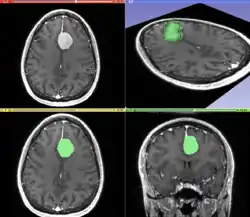

Segmentation

Segmentation is the process of partitioning an image into different meaningful segments. In medical imaging, these segments often correspond to different tissue classes, organs, pathologies, or other biologically relevant structures.[2] Medical image segmentation is made difficult by low contrast, noise, and other imaging ambiguities. Although there are many computer vision techniques for image segmentation, some have been adapted specifically for medical image computing. Below is a sampling of techniques within this field; the implementation relies on the expertise that clinicians can provide.

- Interactive segmentation: Interactive methods are useful when clinicians can provide some information, such as a seed region or rough outline of the region to segment. An algorithm can then iteratively refine such a segmentation, with or without guidance from the clinician. Manual segmentation, using tools such as a paint brush to explicitly define the tissue class of each pixel, remains the gold standard for many imaging applications. Recently, principles from feedback control theory have been incorporated into segmentation, which give the user much greater flexibility and allow for the automatic correction of errors.[9]

- Convolutional neural networks (CNNs): The computer-assisted fully automated segmentation performance has been improved due to the advancement of machine learning models. CNN based models such as SegNet,[14] UNet,[15] ResNet,[16] AATSN,[17] Transformers[18] and GANs[19] have fastened the segmentation process. In the future, such models may replace manual segmentation due to their superior performance and speed.